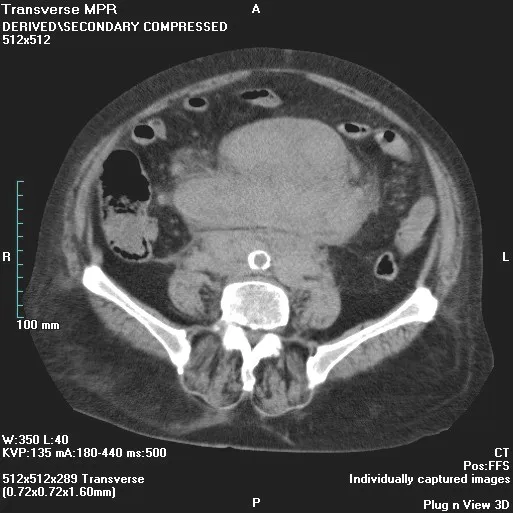

The Essential Role of Imaging in Diagnoses

Medical imaging serves as the first line of sight in detecting anomalies within the lymphatic system. Technologies such as computed tomography (CT) scans and magnetic resonance imaging (MRI) are instrumental in visualizing the extent and location of lymph node involvement. Through detailed images, radiologists can assess the size, shape, and consistency of mesenteric lymph nodes, paving the way for a more targeted approach in subsequent biopsies.

- Utilization of CT and MRI scans to detect lymphoma presence and extent